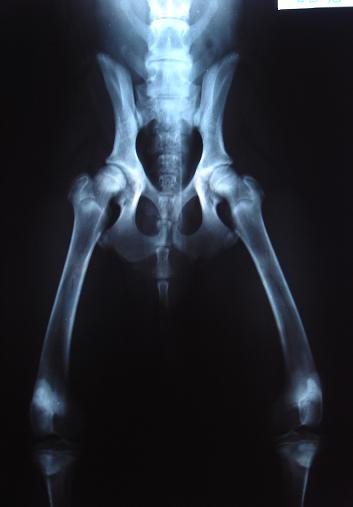

哈哈6個月的時候有去照x光

出來醫生說

膝蓋關節的連接處有分比較開(所以是膝關節???)

髖關節部分只有一點點(骨頭98%是接合的)

醫生說髖關節是後天的.不會遺傳

ㄆ  我有帶哈哈去拍x光 骨頭跟股股頭之間是密合的(只有一點點開.偶會補照片)

所以醫生說是後天ㄉ0.0

因為是密合的所以我才煩惱阿...

如果是分很開就很有可能是先天...

不過看了x光之後又沒異狀...

骨 004444.JPG (23.22 KB)

2007-11-23 14:55

6個月的時候拍的